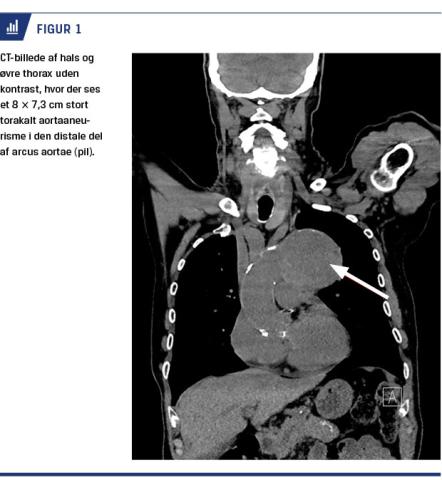

En 87-årig mand henvendte sig til en specialpraktiserende øre-næse-hals-læge pga. hæshed og intermitterende svigt af stemmen gennem to uger. Han havde ingen smerter, klumpfølelse i halsen, hoste eller åndenød. Patienten havde forhøjet blodtryk og var i medicinsk behandling for dette. Endvidere havde han været hospitalsindlagt for et rumperet infrarenalt aortaaneurisme og flere gange pga. akut myokardieinfarkt. Ved objektiv undersøgelse med fiberlaryngoskopi konstateredes venstresidig stemmebåndsparese, hvorfor han blev henvist til et lokalsygehus i kræftpakkeforløb under mistanke om cancer thyroidea. På den lokale øre-næse-hals-afdeling viste en ultralydundersøgelse af halsen en forstørret venstre lap af glandula thyroidea, men ingen afgrænset tumor. Der blev foretaget finnålsbiopsi, som gav mistanke om follikulær neoplasi, og patienten blev viderehenvist til en højtspecialiseret afdeling med henblik på operation. I overensstemmelse med retningslinjerne for pakkeforløb ved stemmebåndsparese blev der ud over objektiv undersøgelse, fiberskopi og ultralydskanning af halsen foretaget en CT af hals og øvre thorax. Skanningen viste normale forhold på halsen, men afslørede et 8 × 7,3 cm stort torakalt aortaaneurisme (Figur 1). Ved akut karkirurgisk tilsyn blev han vurderet at være inoperabel. Pga. begrænset mistanke om malignitet og fund af årsag til paresen blev der afstået fra hemityroidektomi, og patienten fortsatte i et kontrolforløb.